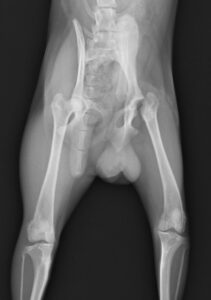

5~6歳以上の去勢手術をしていないオス犬に多い病気ですが、メス犬や去勢した犬に起こることもあります。お尻の筋肉が萎縮した結果、筋肉の隙間から直腸や膀胱が皮膚の下にとびでてしまいます。これにより便が出にくくなったり膀胱炎になったりします。手術をすることで機能回復および今後の致死的な状況を回避することができます。当院では去勢手術→結腸固定→前立腺固定→骨盤隔膜構成筋の縫縮→内閉鎖筋フラップ→浅臀筋フラップの順で通常腹側・臀部左右両側同時に行います。また老化以外に、筋肉が萎縮する原因があったり、腹圧がかかる原因があったりする場合も多いので、再発防止のためそれらの診断・治療も重要です。今回のワンちゃんも無事手術も終わり元気に退院しました。よかったね。